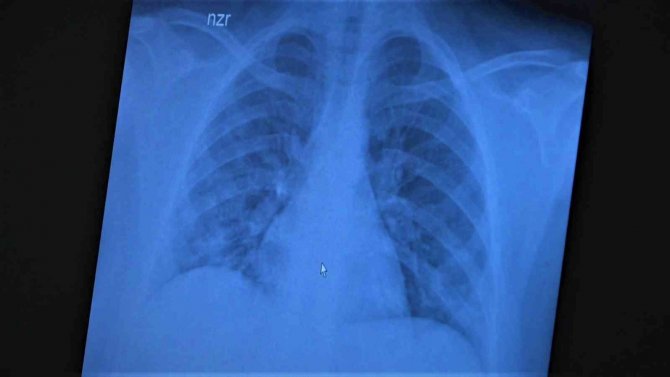

Çocukların akciğer tomografilerini inceleyen Özkaya, "11 yaşında kovid pozitif bir öğrencimiz, yüksek ateş ve nefes darlığı ile bize geldi. Ciddi akciğer tutulumu var. Geçen yıl "bu çocuklar hastalıktan etkilenmiyor" diyorduk. Bu çocukta görüyorsunuz buzlu camlar ve konsolidasyon alanlarla seyrediyor. Geçen yıl bu şekilde çok çocuk görmüyorduk. Önümüzdeki aylarda bu şekilde devam ederse çocuklarımızı kaybetmeye bile başlayabiliriz. 14 yaşında pozitif olan bir diğer çocuğumuz ise aşı randevusu almış ama aşısını olmadan ateş ve öksürükle başvurdu. Halen şanslıyız. Çocuklar çok hızlı tedaviye yanıt veriyor. Düzeldi. Çekilen tomografisinde ise bilaterel yaygın tutulumları vardı. Bu ise 24 yaşında genç hastanın akciğer tomografisi. Bu kişide yaygın akciğer tutulumları görüldü. Bunu da tedavi ettik. Önümüzdeki aylarda ne getirecek ne götürecek beraber göreceğiz. Özellikle havaların soğumasıyla kapalı ortamlarda geçilen zamanın ve kalabalıkların etkisiyle vaka sayılarının önümüzdeki günlerde artacağını biliyoruz. Şu an gerçekten hastalık gençlerde 30 -40 yaş altı gençlerde görülmeye başladı. Poliklinik şartlarında olanların büyük bir kısmı 30 yaş altı hastalar. Servislerde yatanlarda orta yaş ve altı nüfus. Yoğun bakımda yatanların büyük bir kısmı ise aşısız erişkin insanlardan oluşuyor" diye konuştu.